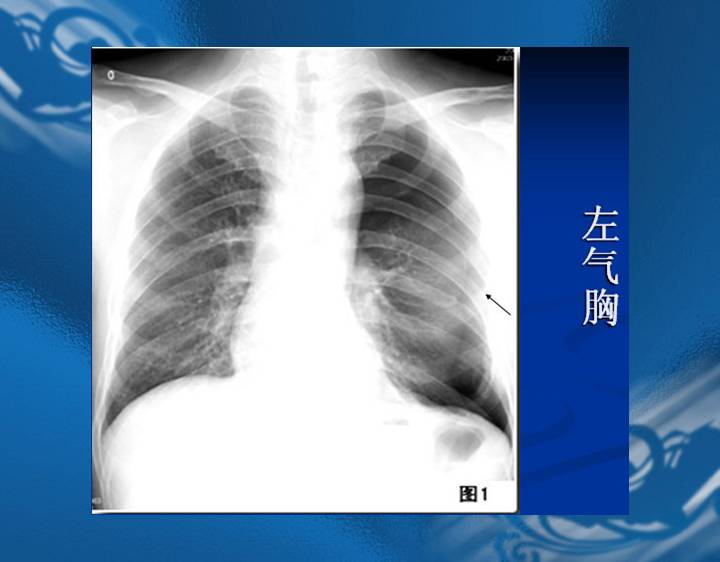

执业医师资格考试“实践技能”影像学辅导资料